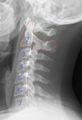

Cervical vertebrae lateral2.png

موقع الفقرة العنقية البشرية (موضحة بالأحمر). تتكون من 7 عظام، من أعلى إلى أسفل، C1، C2، C3، C4، C5، C6 وC7.